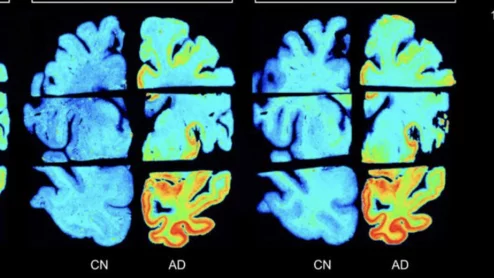

alzheimer's disease dementia brain imaging

The reasons for misdiagnoses are wide-ranging, but interpretations of patients’ brain imaging may play a prominent role.